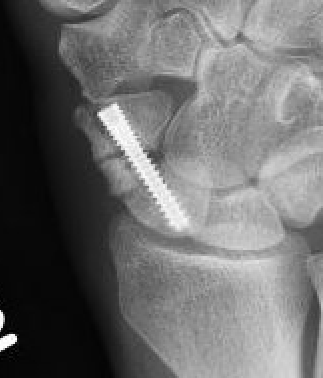

Post scaphoid ORIF

Xray

Proximal pole nonunion with displacement and absorption